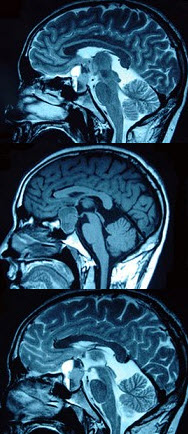

130、单项选择题

男,47岁,头痛三年余,最近2个月感觉视力下降,MRI检查如图,最可能的诊断为()

A.垂体瘤

B.颅咽管瘤

C.垂体囊肿

D.垂体腺瘤囊变

E.脑膜瘤